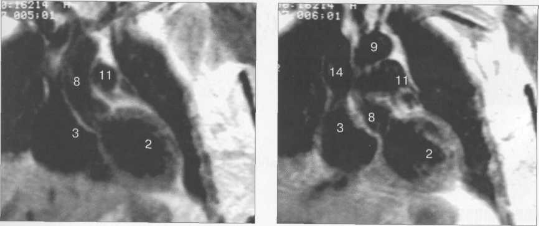

Рис. 9.47. МРТ сердца. Аксиальная плоскость.

Здесь и на рис. 9.48—9.52:

I — правый желудочек, 2 — левый желудочек, 3 — правое предсердие, 4 — левое предсердие, 5 — межжелудочковая перегородка, 6 — межпредсердная перегородка, 7 — задняя стенка левого желудочка, 8 — восходящая часть аорты, 9 — дуга аорты, 10 — нисходящая часть аорты, 11 — легочный ствол, 12 — правая легочная артерия. 13 — левая легочная артерия, 14 — верхняя полая вена, 15 — нижняя полая вена, 16 — трахея.

Рис. 9.48. MPT сердца. Сагиттальная плоскость.

Рис. 9.49. МРТ сердца. Двухкамерные сечения.

Рис. 9.50. МРТ сердца. Фронтальные сечения.

Рис. 9.51. МРТ сердца. Сечения по короткой оси левого желудочка.

Рис. 9.52. МРТ сердца. Четырехкамерные сечения.

На рис. 9.47—9.52 представлены Т1-ВИ наиболее часто используемых МР-сечений сердца.